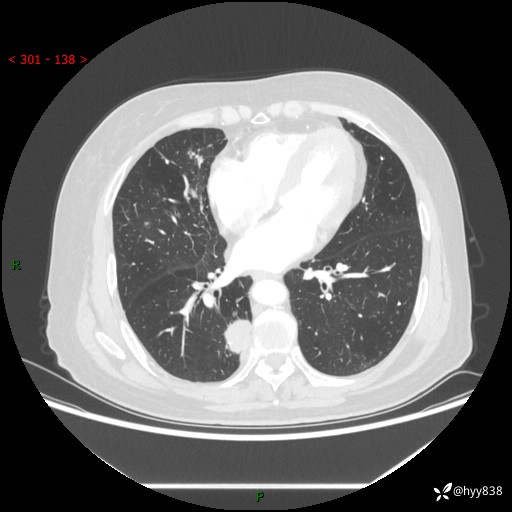

胸部CT肺窗(平扫外院)

增强动脉期+静脉期

两期CT值:55Hu 53hu